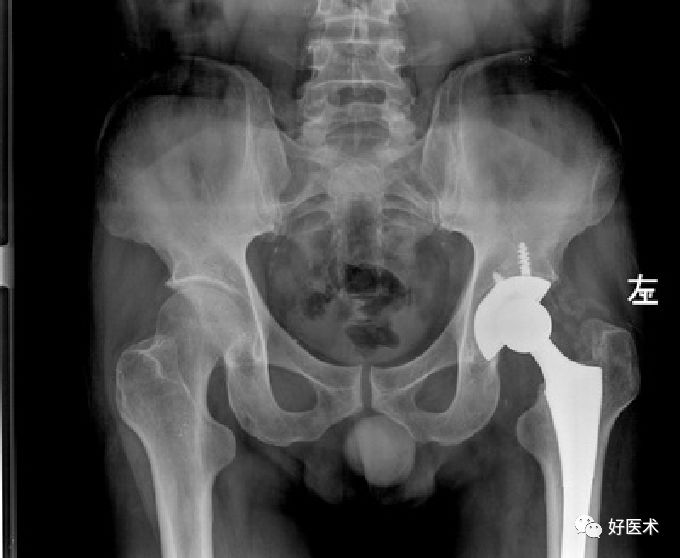

患者,男,69岁,因“摔伤致左髋部疼痛伴活动受限3小时”为主诉于今年10月12到我院急诊科就诊。急诊行X线片检查示:“左侧股骨颈骨质连续性中断”。

入院查体:

-

T:36.5℃ P:80/min R:18/min BP:135/80mmHg;

患者神志清楚,精神可,心肺腹查体未及明显异常。脊柱无畸形,骨盆挤压试验分离试验阴性,右下肢呈短缩外旋畸形,外旋约40°,较健侧肢体短缩约2cm。右髋部稍肿胀,无明显的瘀斑。右侧腹股沟中点压痛阳性、轴向叩击痛阳性。右侧Bryant三角底边较健侧短缩。膝关节、踝关节活动尚可无压痛,趾端感觉正常,余肢体未及异常。

Garden分型?

Ⅳ型

内固定 OR 髋关节置换?

髋关节置换

全髋 or 半髋?

股骨头置换

骨水泥 OR 非骨水泥?

非骨水泥假体